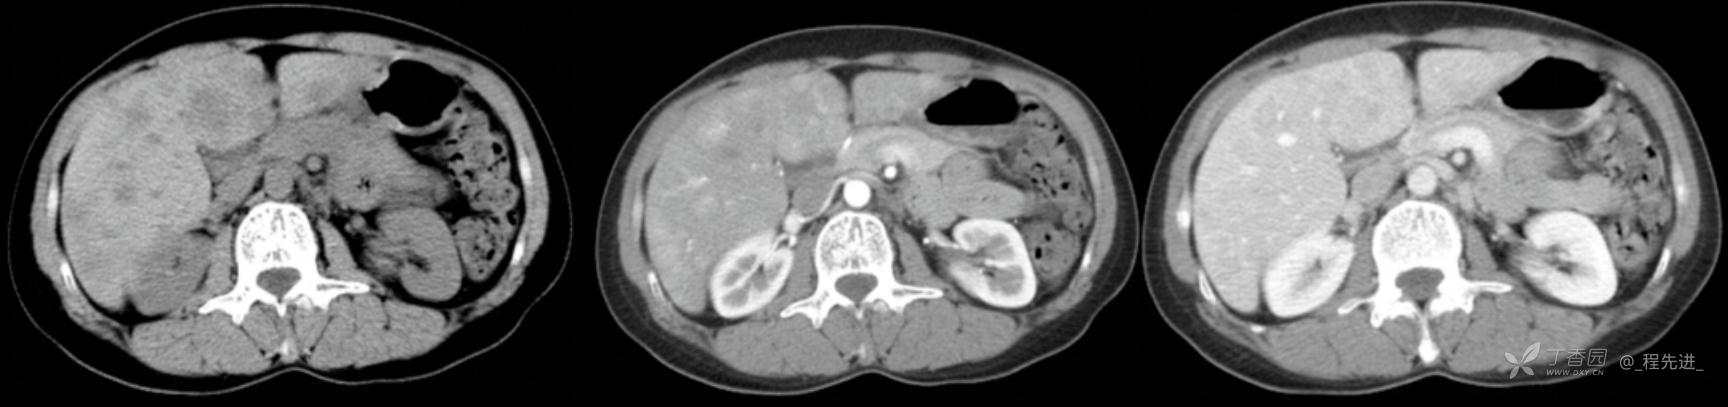

图像左边为平扫,中间的是动脉期,右边的是静脉期